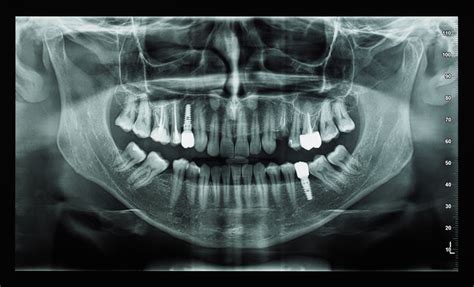

La ortopantomografía es un estudio radiológico en donde es posible observar todos los dientes, tejidos de soporte y estructuras anatómicas adyacentes. Es una imagen bidimensional de un objeto tridimensional, por lo que las imágenes se pueden superponer. Aunque es una radiografía muy útil para un diagnóstico inicial, esta superposición algunas veces, impide una visualización detallada de ciertas patologías.

En una radiografía panorámica se pueden ver una infinidad de estructuras anatómicas. Para empezar, podemos ver tanto los dientes superiores como los inferiores y sus respectivas raíces. A continuación podemos ver el hueso, clave en la colocación de implantes.

A partir de aquí en la ortopantomografia se pueden ver una infinidad de estructuras anatómicas. Entre ellas encontramos:

Ejemplo de radiografía panorámica con estructuras anatómicas señaladas.